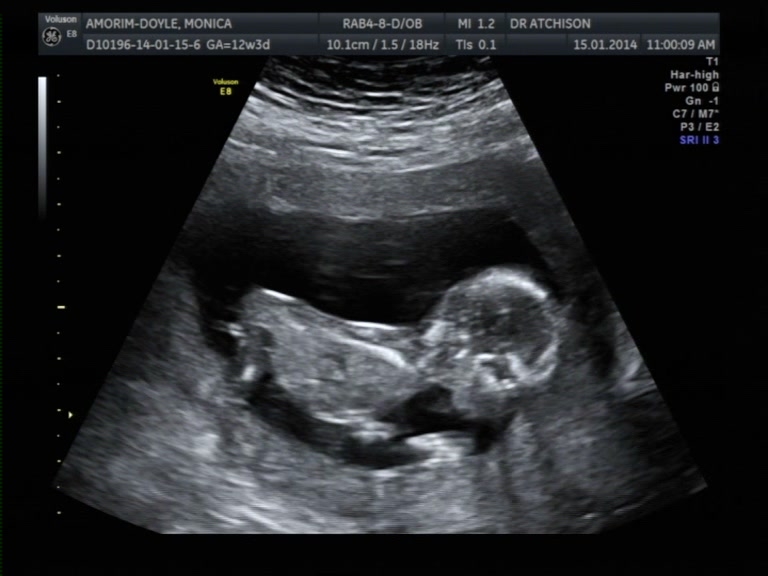

I already posted my ulstrasound picture but nub couldn't be seen, and as the obsessive human being I am I took pictures frame by frame using the video and I came up with some nub shots, BUT, I am not sure how to or even if I should regard a nub when baby is tummy down. I heard you 'read' the nub in relation to the spine. If you have a guess, regardless, I would be very happy. :)

Attachment 16360

IT'S A GIRL!!!!!!!